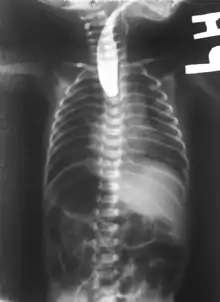

On plain X-ray, a feeding tube will not be seen pass through the esophagus and remain coiled in the upper oesophageal pouch.[8]

If any of the above signs/symptoms are noticed, a catheter is gently passed into the esophagus to check for resistance. If resistance is noted, other studies will be done to confirm the diagnosis. A catheter can be inserted and will show up as white on a regular x-ray film to demonstrate the blind pouch ending. Sometimes a small amount of barium (chalk-like liquid) is placed through the mouth to diagnose the problems.